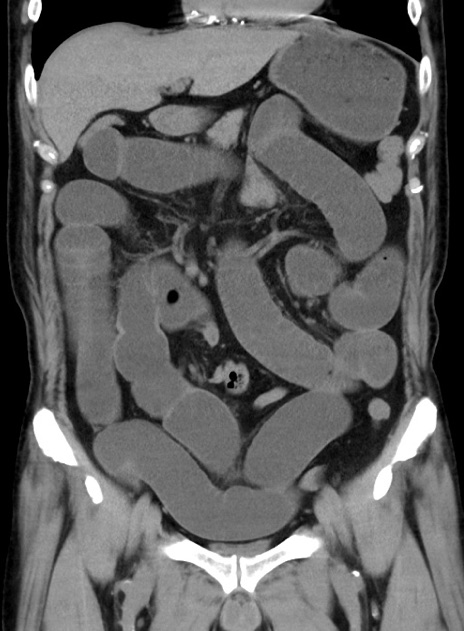

横断像

【症例】70歳代 男性

【主訴】腹痛・嘔吐

【現病歴】昨晩より、嘔吐・腹痛あり。今朝になっても嘔吐あり。来院。

【既往歴】心臓バイパス手術、開腹胆摘、腸閉塞

【身体所見】BP 107/71mmHg、HR 116/min、腹部:平坦、軟、下腹部に軽度圧痛あり。反跳痛なし。

【データ】WBC 15100、CRP 0.32